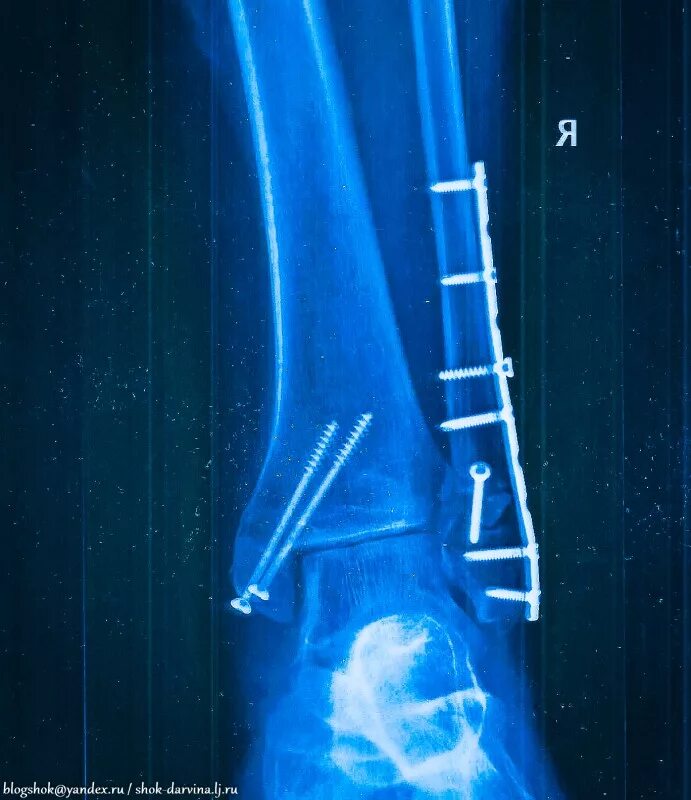

После остеосинтеза лодыжек